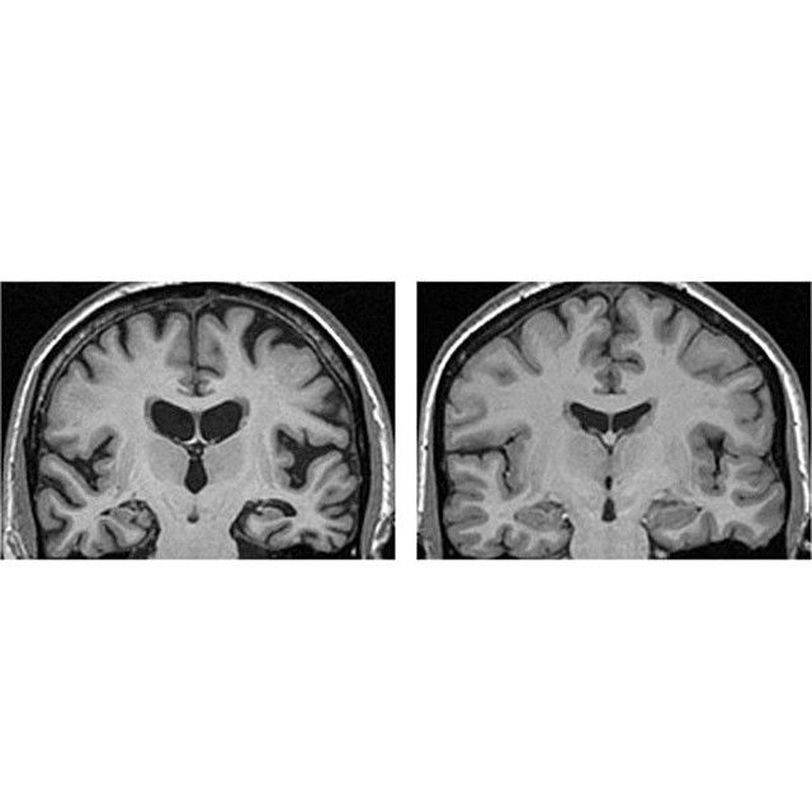

Loss of brain tissue (atrophy/degeneration) is seen well, shrinkage of the cerebral gyri of the temporal and parietal lobes, as well as the corpus callosum, fornix, caudate nucleus, and the hippocampus. All of which causes the dilation of the lateral and third ventricles (in the middle). Alzheimer's is a chronic neurodegenerative disease, and it's the most common cause of dementia, a general term for memory loss and other intellectual abilities. It's important to know that it's a progressive disease, where dementia symptoms gradually worsen over a number of years. In its early stages, memory loss is mild, but with late-stage Alzheimer's, individuals lose the ability to carry on a conversation and respond to their environment. The cause is poorly understood. It is believed that a build-up of beta-amyloid plaques and neurofibrillary tangles in the brain are associated with the disease. Other risk factors include a history of head injuries, depression or hypertension.No cure for Alzheimer's, but there are medications that slow the progression of the disease and manage the symptoms.